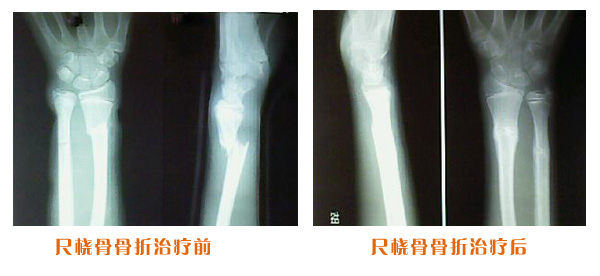

尺橈骨克雷氏骨折治療前后